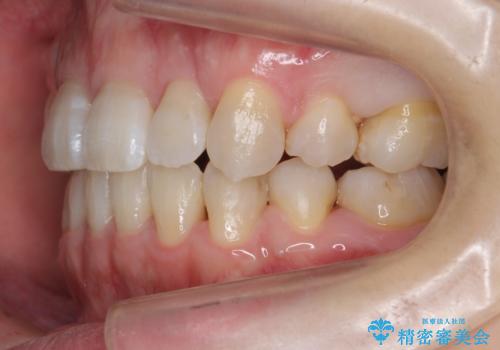

ハーフリンガル 犬歯のねじれ 歯根の外部吸収している歯を抜歯

- 前歯のねじれを主訴に来院。

レントゲンを撮影したところ、右下4は神経のない歯で、外部吸収といって、根がだんだん短くなり、やがて抜けてしまう症状になっていました。また、アンキローシスを起こしている可能性があるため、動かない可能性が高い状態でした。

矯正治療で右下を抜歯し、スペースを天然の歯でつめる矯正治療を行いました。